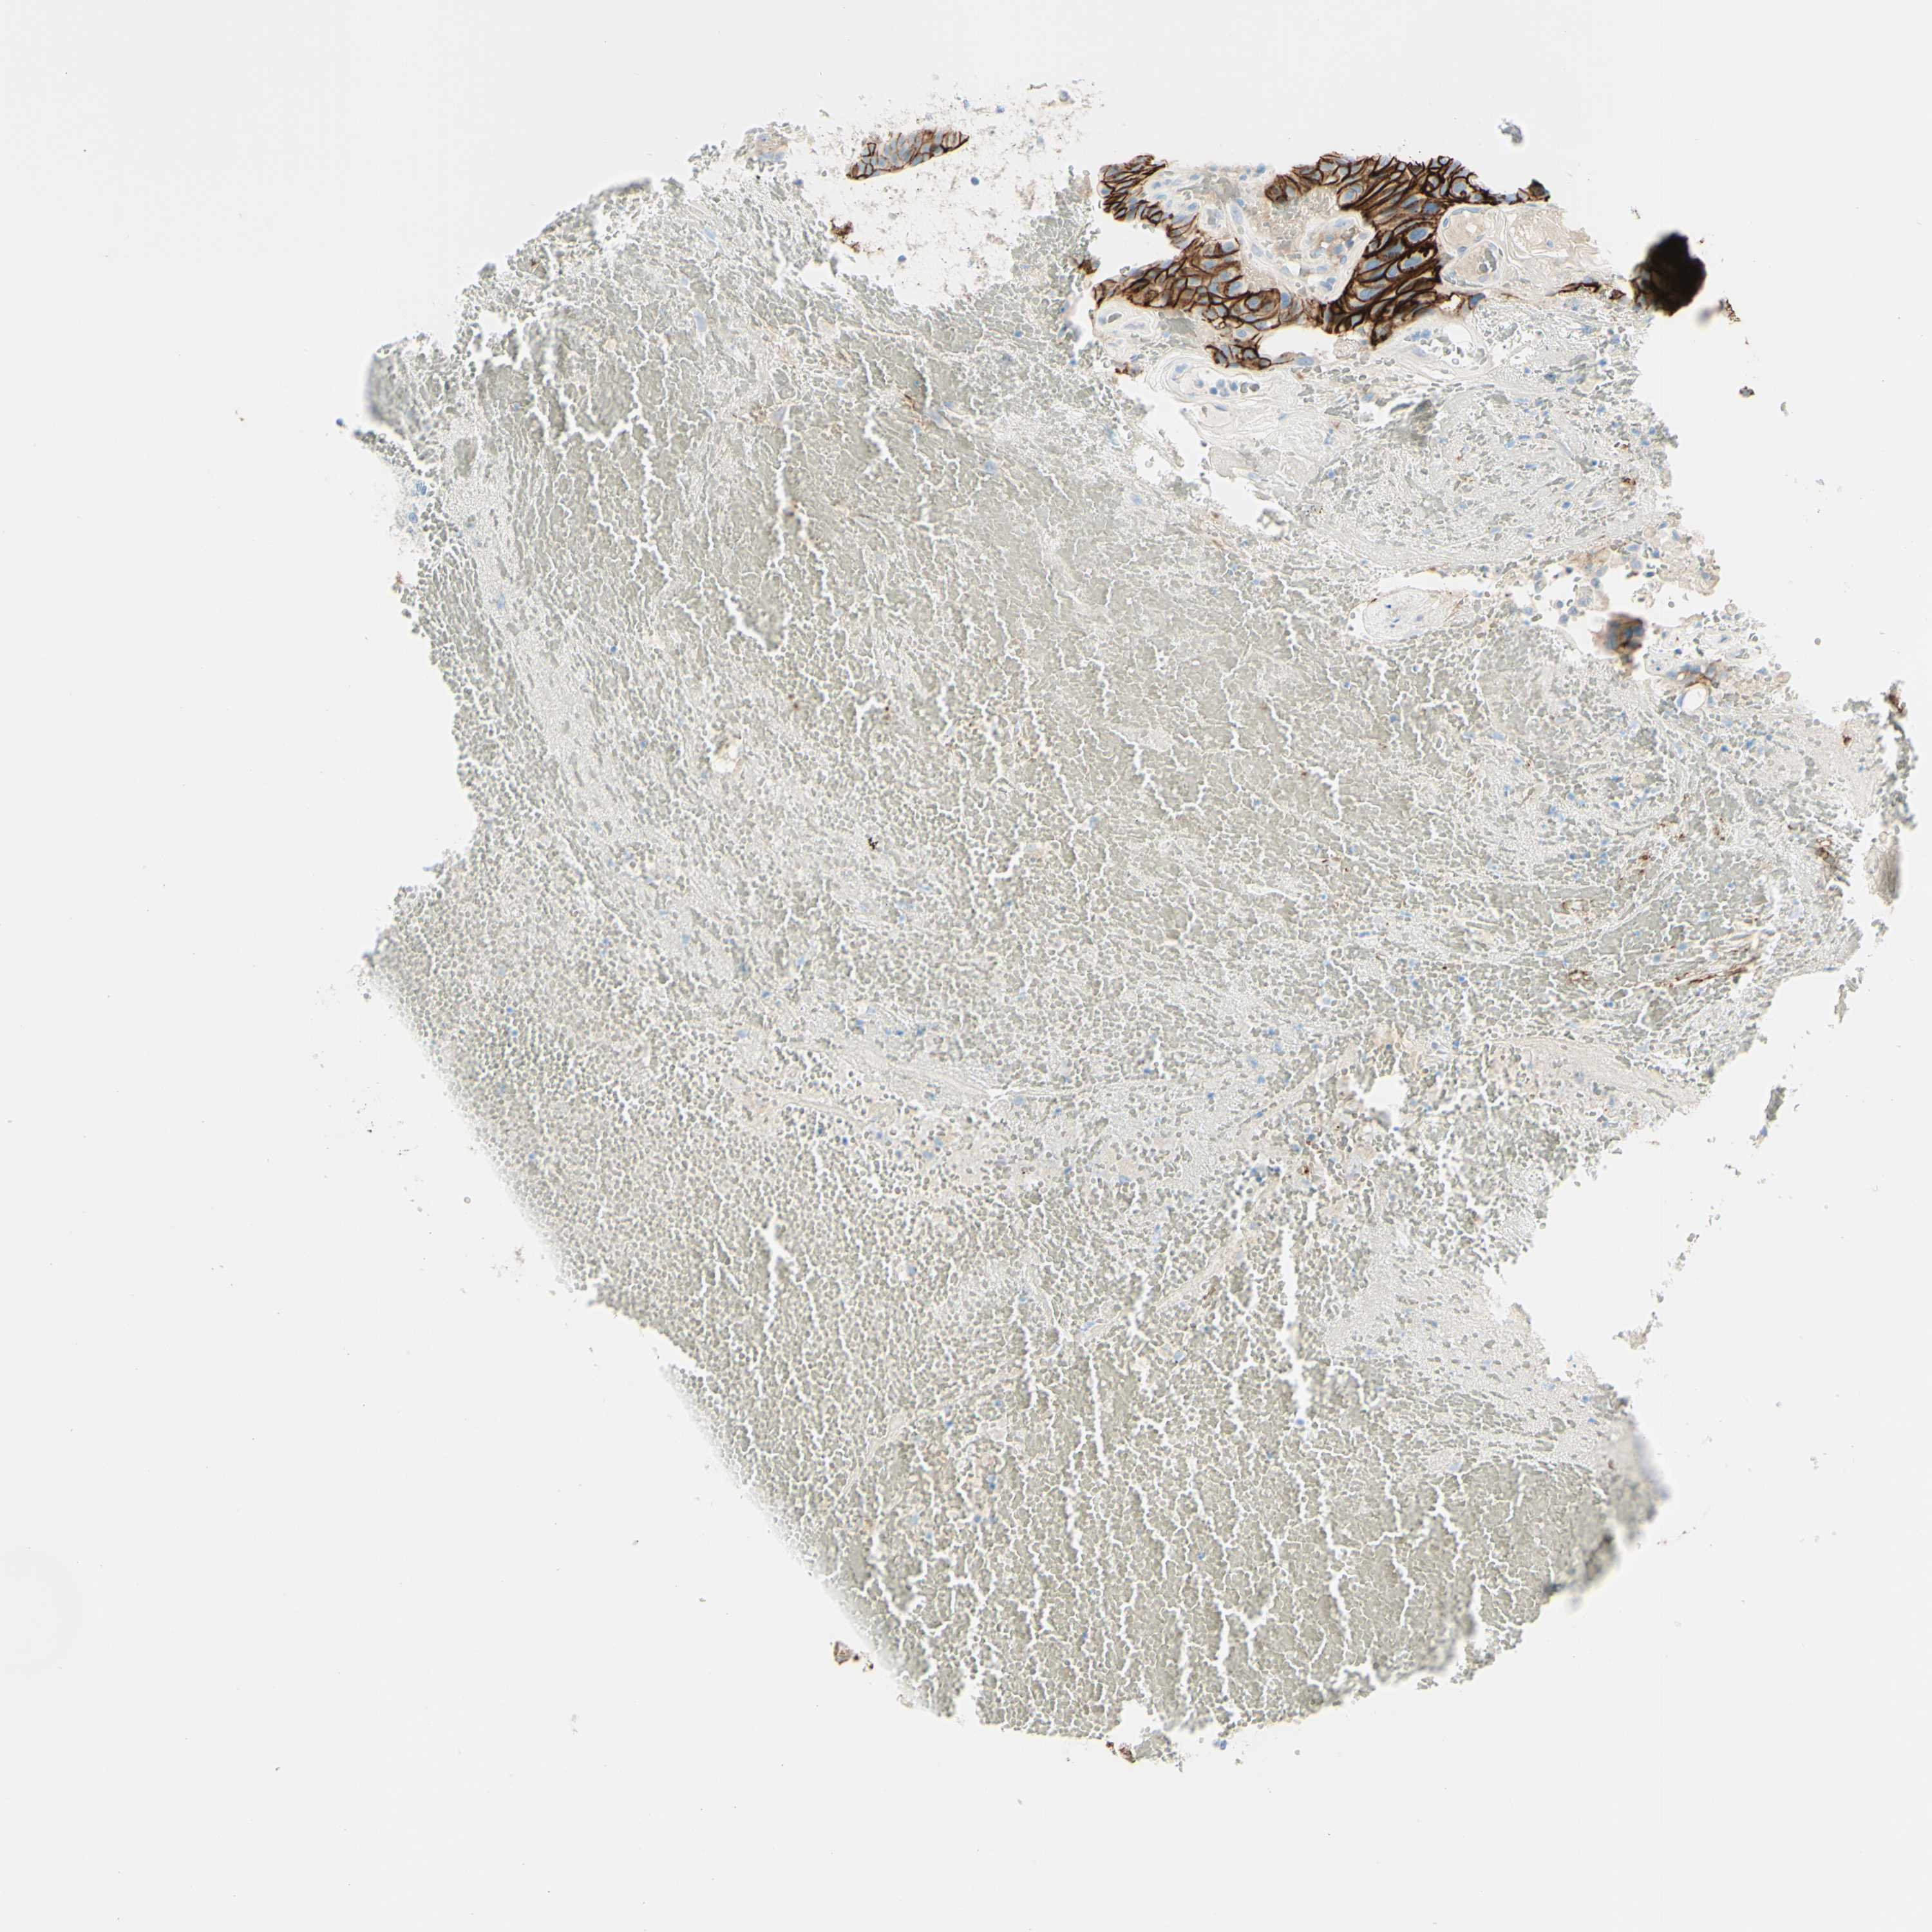

UROTHELIAL CANCER - Protein expressioni

A mouse-over function shows sample information and annotation data. Click on an image to view it in a full screen mode. Samples can be filtered based on level of antibody staining by selecting one or several of the following categories: high, medium, low and not detected. The assay and annotation is described here.

Note that samples used for immunohistochemistry by the Human Protein Atlas do not correspond to samples in the TCGA dataset.

Antibody stainingi

Antibody staining in the annotated cell types in the current human tissue is reported as not detected, low, medium, or high, based on conventional immunohistochemistry profiling in selected tissues. This score is based on the combination of the staining intensity and fraction of stained cells.

Each image is clickable and will lead to virtual microscopy that enables deeper exploration of all samples and also displays staining intensity scores, fraction scores and subcellular localization as well as patient and tissue information for each sample.

Antibody HPA010926

Antibody CAB002148

Urothelial carcinoma, Low grade

Urothelial carcinoma, High grade

Adenocarcinoma, NOS